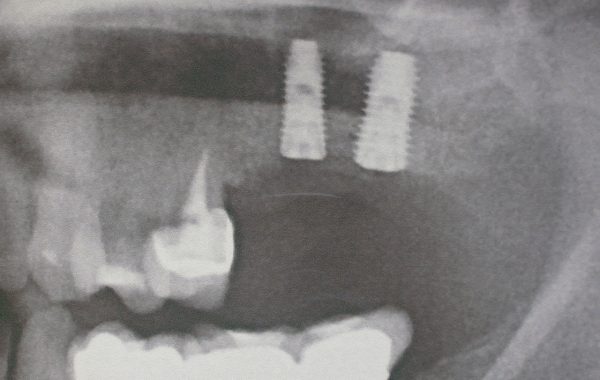

Aquí presentamos una radiografía de un paciente de que perdió los dos molares superiores izquierdos.

Aquí se observa la poca cantidad de hueso por debajo de los senos maxilares

Nótese el injerto colocado obteniendo mayor altura para la colocación de los implantes